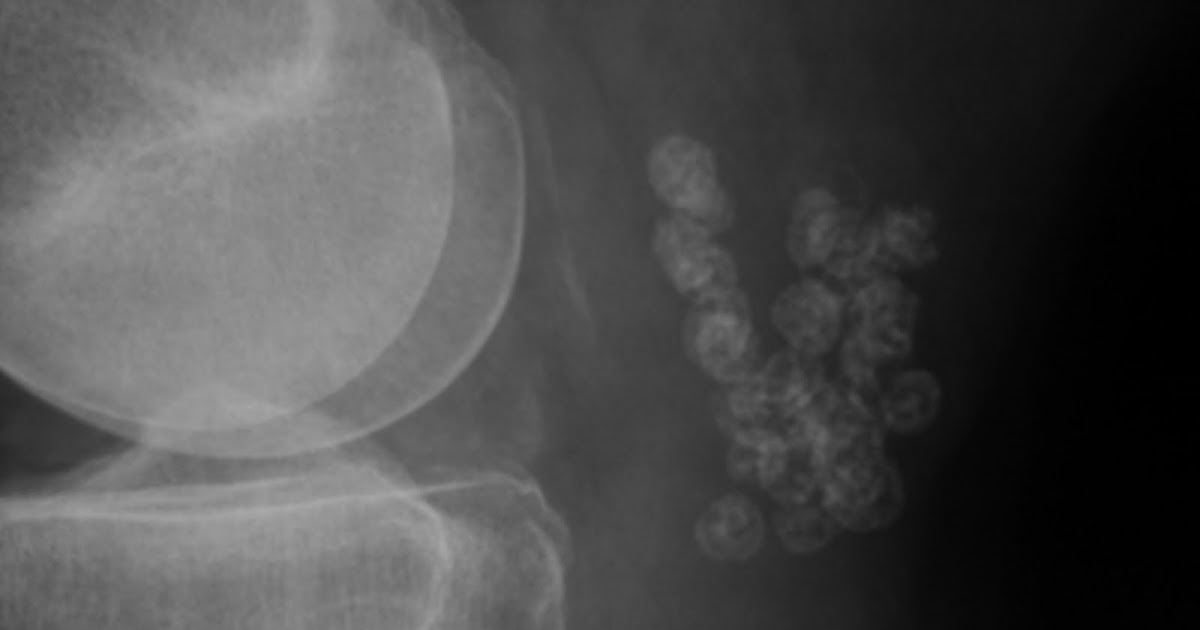

Daily Dose ? Synovial osteochondromatosis of Baker's cyst Baker's Cyst 7 Year Old Learn about the possible causes, how to treat it conservatively or surgically, and. They can be primary or secondary to underlying joint disease and may. Find out when to see your gp and what other options are. Learn how to treat a baker's cyst at home with ibuprofen, ice, rest and a knee support. It occurs when fluid builds up. Baker's Cyst 7 Year Old.